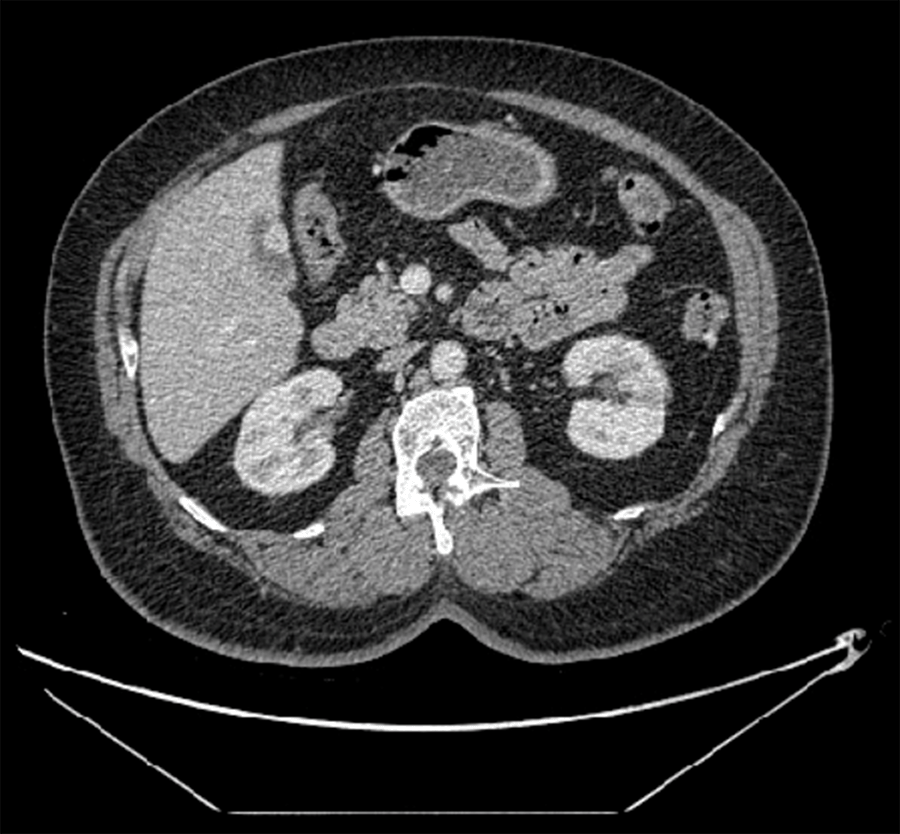

The patient is a 67-year-old female with a history of hypertension, diabetes, and hyperlipidemia. She initially presented to our hospital for epigastric pain and, on ultrasound, was found to have a vascular lesion of the anterior gallbladder wall that measured 1.0 × 1.3 cm (Figure 1). At that time, the concern was for gallbladder polyp versus malignancy. Her laboratory findings were significant for a mildly elevated ALT, AST, and alkaline phosphatase but normal bilirubin. The patient was given a referral to follow-up in the surgery clinic but never presented.

Figure 1. Transverse View of Well-Vascularized Gallbladder Lesion. Published with Permission